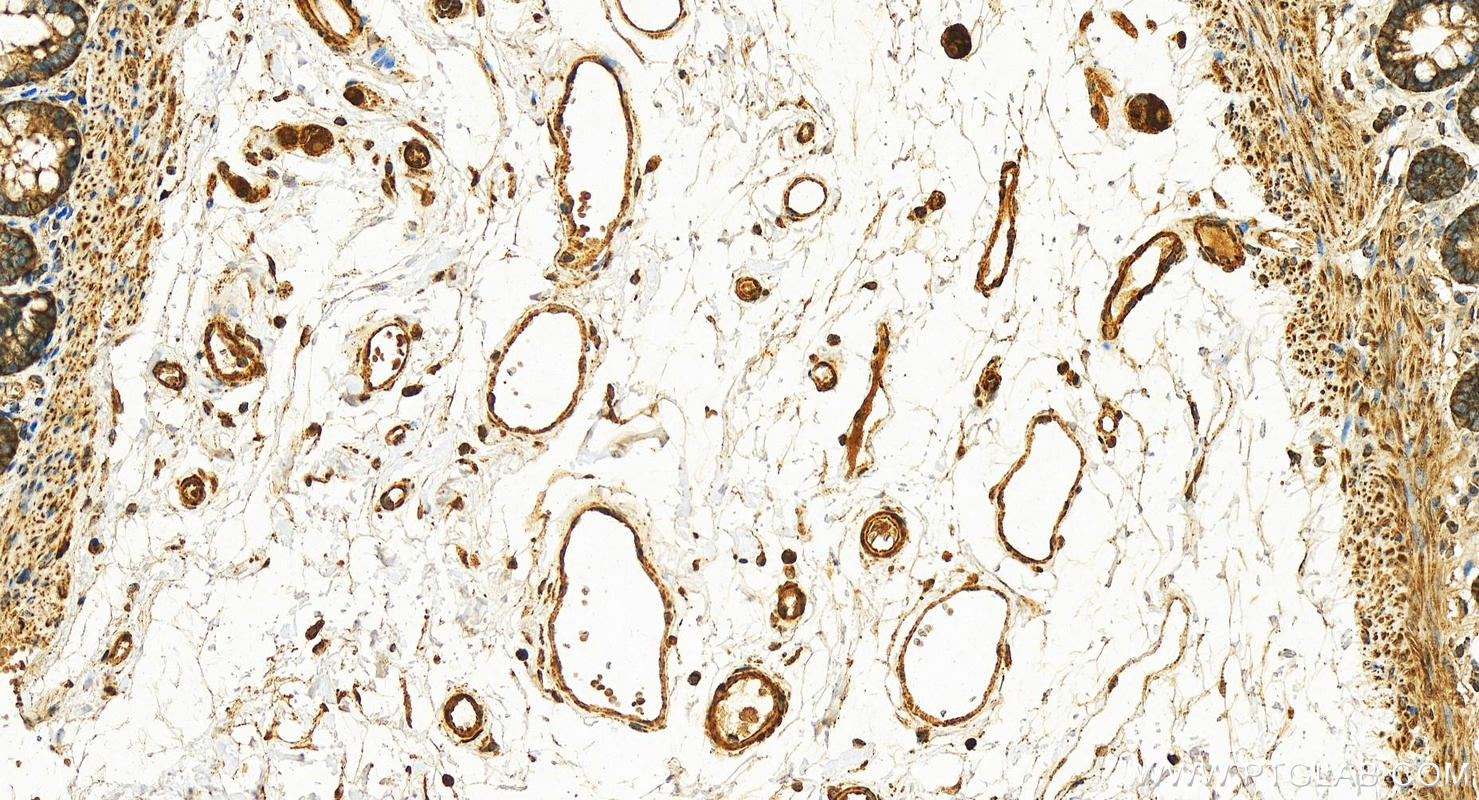

Validation Data Gallery View All